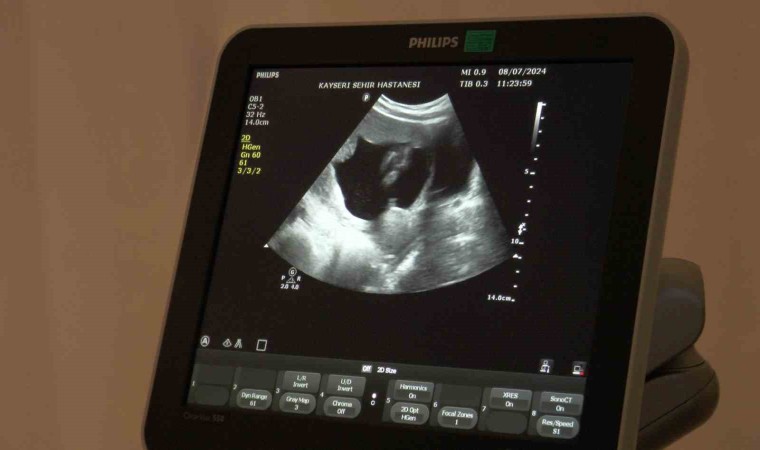

Doç. Dr. İlknur Çöl Madendağ,merkezde hastaya tedavi uygulamadan önce planlamaları yaparak bilgilendirdiklerini ve ortak karar ile tedavi uyguladıklarını söyleyerek, “Aslında hastalarımızın çoğu merkezimize tüp bebek yaptırma istemi ile gelmekte ama biz hastalarımızı değerlendirdikten sonra durumları hakkında ayrıntılı bilgi verip, tabi son tercihi onlara bırakmakla beraber, bilimsel veriler ışığında tıbbi durumu ne gerektiriyorsa öncelikle onu öneriyoruz hastalarımıza. Öncelikle tıbbi durumu hakkında hastalarımızı bilgilendirip önerimizi yapıyoruz ve onun isteği ile ortak kararımızı verip tedavimizi uyguluyoruz. Burada da hastamızın azalmış yumurtalık rezervi dediğimiz yumurta sayısı azlığı ve geçirilmiş dış gebelik, düşük, rahim tüp iltihabı, enfeksiyon durumları gibi sıkıntıları vardı. Bize geldiğinde önce ayrıntılı muayenesini yapıp gerekli tetkiklerinin ardından cerrahi müdahalesini planladık. Hastamızın azalmış yumurta sayısı vardı ama öncelikle rahim tüp filmini çektiğimize tüplerinde sıvı toplaması olduğunu ve kapalı olduğunu gördük. Yaptığımız ameliyatta tüpünün tıkalı olduğunu teşhis edip o sıvı toplamış tüpü aldık. Diğer tüpünün açık olduğunu gördükten sonra enfeksiyon tedavisini de yaptık. Yumurtalık gelişimini ve zamanlamasını ayarlayarak tüp bebek tedavisine gerek kalmadan gerekli antibiyotedavisini de verdikten sonra spontan gebeliğe 2 ay gibi kısa bir zaman içinde ulaştık. Geçirilmiş iltihabı vardı ve buna bağlı dış gebeliğinin oluştuğu yerde sıvı toplaması vardı. Bu da engel olan bir durumdu. Sonrasında hastamızın yumurta sayısını tekrar saydık. Gerekli destek tedavilerini verdik ve gebeliğine ulaştık. Şu an 16 haftalık gebeliği mevcut ve sağlıklı bir şekilde gidiyor” dedi.